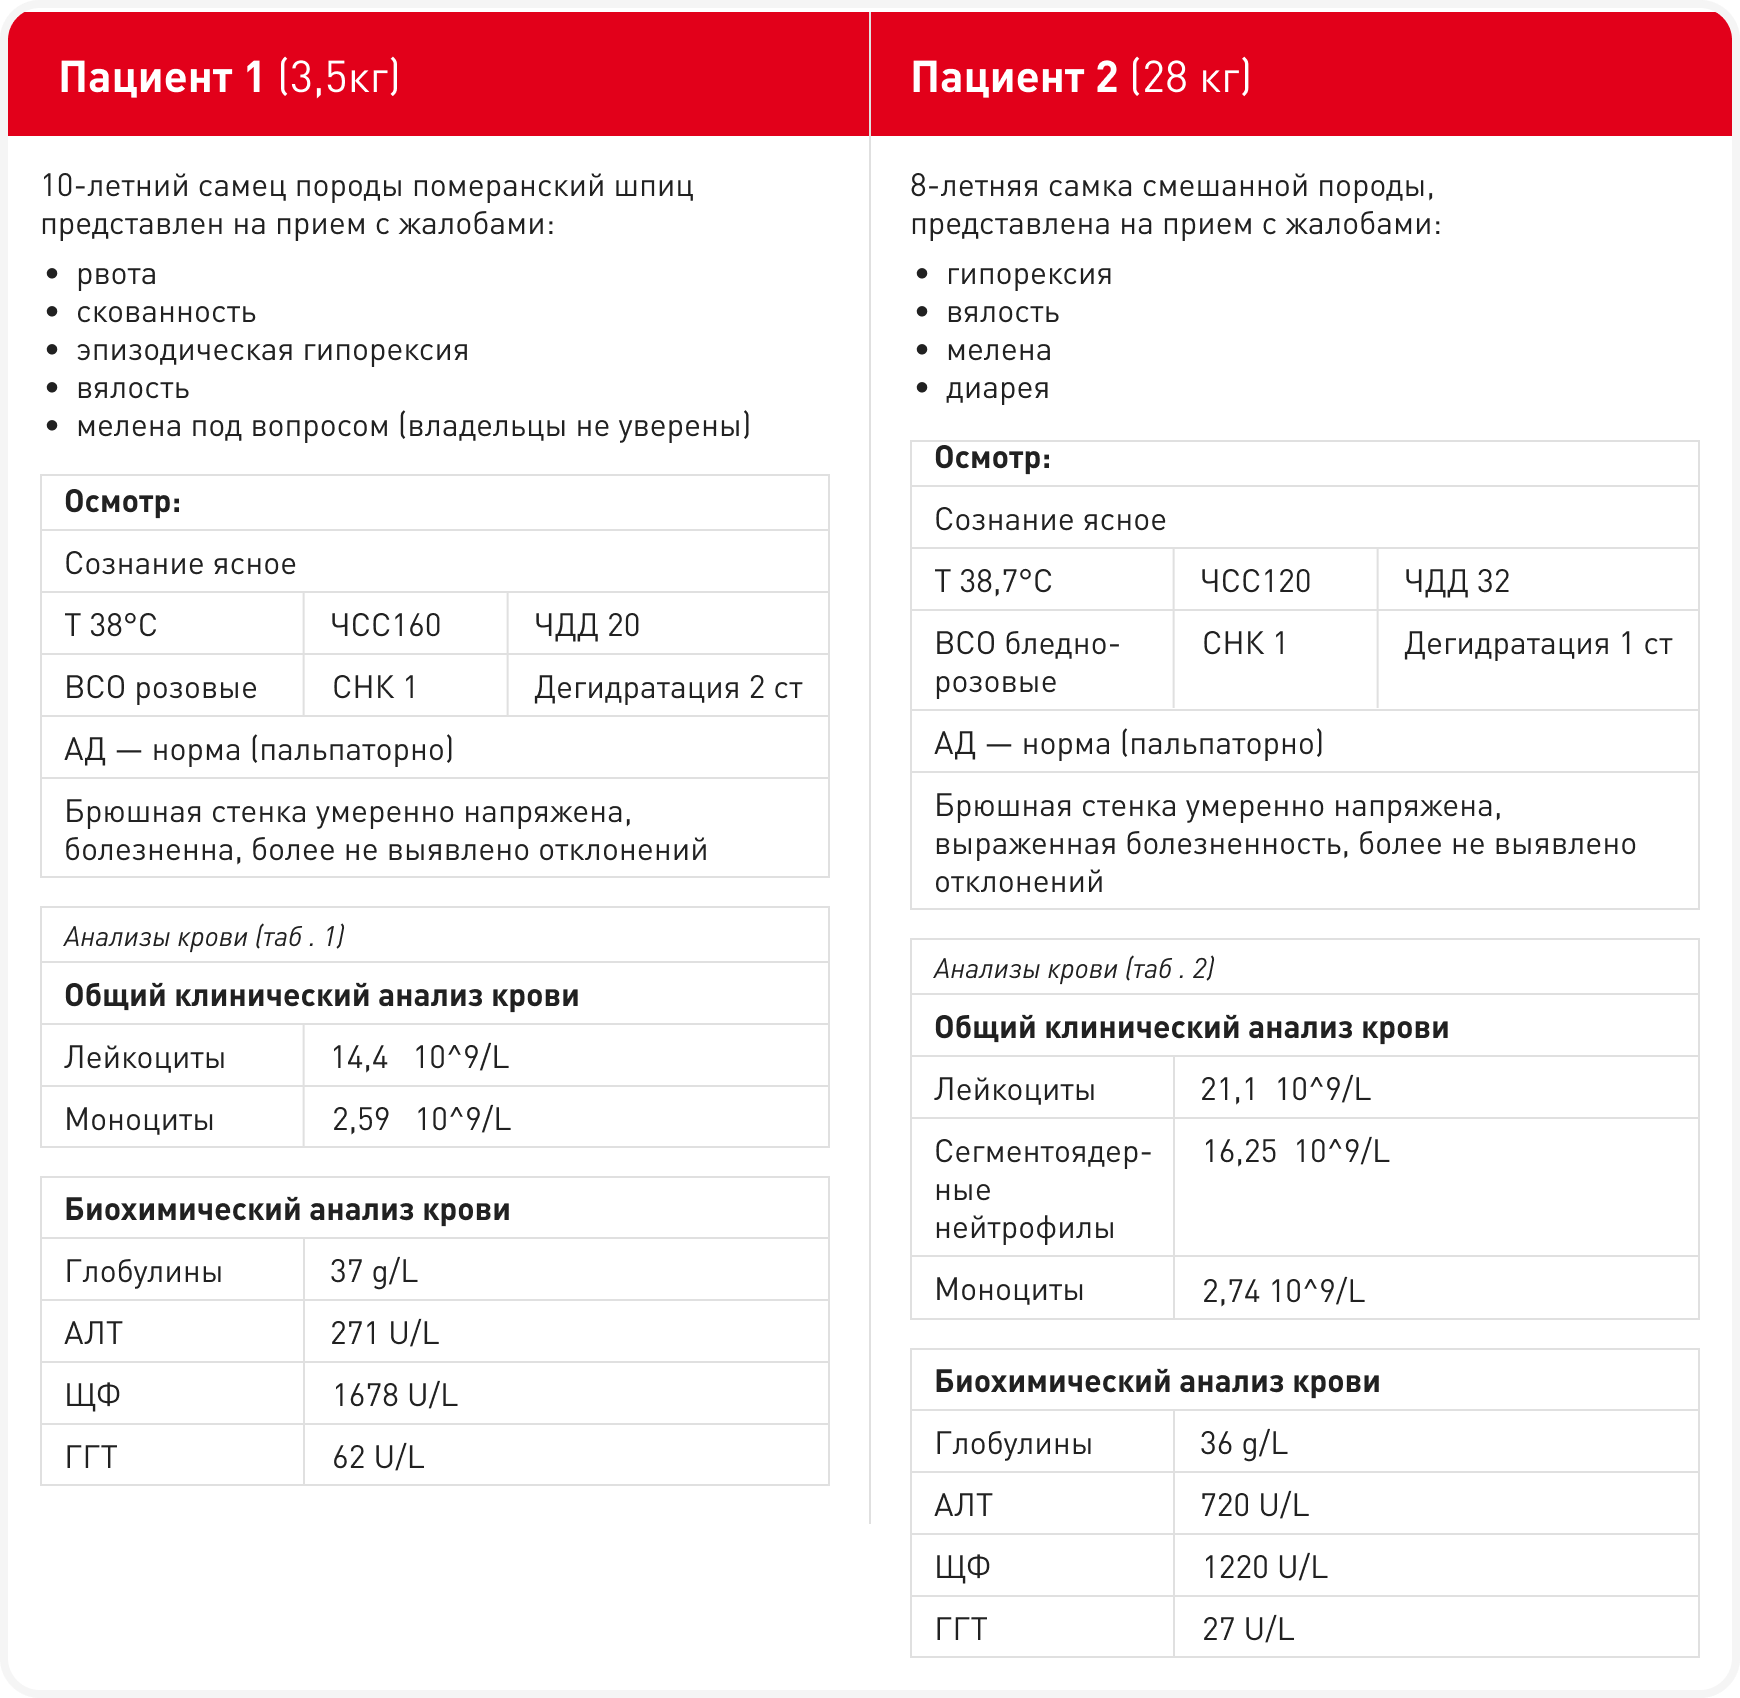

Данные анамнеза представленных клинических случаев

Оба пациента были отправлены на УЗИ (рис.1-2 соответственно) для дальнейшей диагностики лейкоцитоза и повышения ферментов.

Исходя из представленных клинических случаев общими симптомами некротизирующего холецистита были абдоминальная боль, гипорексия, летаргия, а также, возможно, мелена, что не является типичным симптомом. Несмотря на подтвержденный некроз стенки желчного пузыря и холестаз ни у одного пациента не было выявлено гипербилирубинемии и как следствие желтушных слизистых. Также не наблюдался и лейкоцитоз с повышением юных форм нейтрофилов в крови.

Общими отклонениями в анализе крови являлись: лейкоцитоз с повышением моноцитов, гиперглобулинемия, повышение АЛТ, ЩФ, ГГТ. На ультразвуковом исследовании желчный пузырь имел: сильное наполнение, округлую форму, выраженную слоистость стенок с нарушением дифференциации от содержимого, гетерогенные структуры в просвете (вероятно, представленные сгустками или холелитами), а также локальный стеатит с затуханием эхо-сигнала и свободную жидкость, что указывало на остроту процесса.